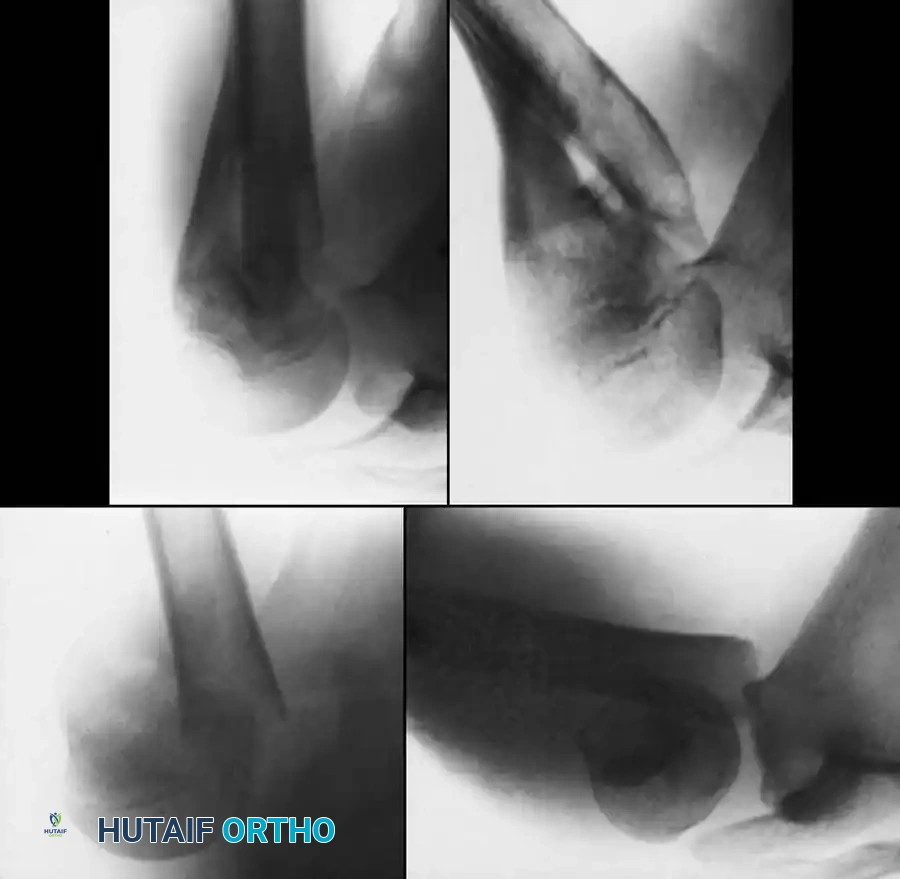

Fig. 33-95 Closed reduction and percutaneous pinning of a proximal physeal separation. Two smooth wires cross the physis to provide rotational and angular stability while minimizing physeal damage.